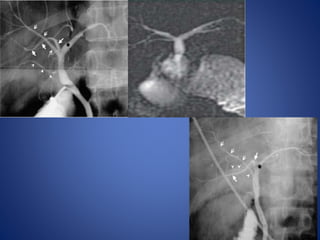

Anomalies of the biliary system are found in 2.4% of autopsies, 28% of

surgical dissections, and 5% to 13% of operative cholangiograms.

• #39 Normal and aberrant sectoral ductal anatomy. (A) Typical ductal anatomy, (B) triple confluence, (C) Ectopic drainage of a right sectoral duct into the common hepatic duct (C1, right anterior duct draining into the common hepatic duct; C2, right posterior duct draining into the common hepatic duct), (D) ectopic drainage of a right sectoral duct into the left hepatic ductal system (D1, right posterior sectoral duct draining into the left hepatic ductal system; D2, right anterior sectoral duct draining into the left hepatic ductal system, (E) absence of the hepatic duct confluence, (F) absence of right hepatic duct and ectopic drainage of the right posterior duct into the cystic duct.

• #40 Diagrams depicting types of commonly encountered biliary variants in decreasing order of their occurrence. A, Normal pattern. B, Right posterior hepatic duct enters the left hepatic duct (19% of normal population). C, Trifurcation (11% of the normal population). D, Right anterior hepatic duct enters the left hepatic duct. E, Low formation of common hepatic duct. F, Right hepatic duct enters cystic duct.